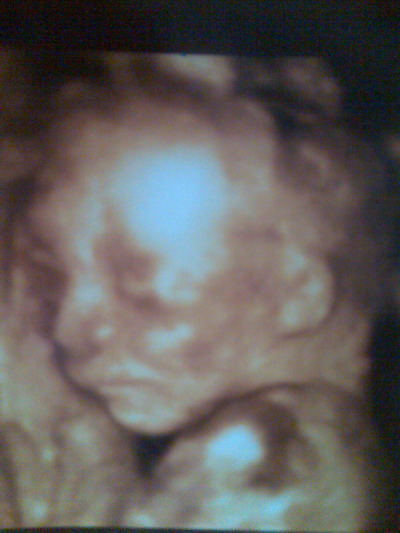

Alíz, nagyon jó ez a kép, Ato baba is csak profilból mutatta magát a 4d-n, többnyire minden baba..

A pocid is szépen alakul, pont ilyen volt az enyém is félidősen

Judy, gyönyörű ez a kislányka, és nagyon hasonlít Rád!!! Komolyan. Sajnálom, hogy betegek lettek a fiúk, ti nem kaptátok el a pároddal?